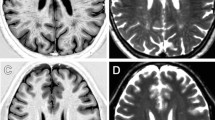

Data were obtained from 42 patients (mean age = 42.4 ± 12.9, M/F = 16/26) and 49 healthy controls (HC-mean age = 42.3 ± 16.3, M/F = 28/21) (Fig. 1). A complete list of demographic and clinical information of the studied population is available in Table 1. Representative R1 images are shown in Fig. 2. A graphical representation of the MRI data analysis is shown in Fig. 3.